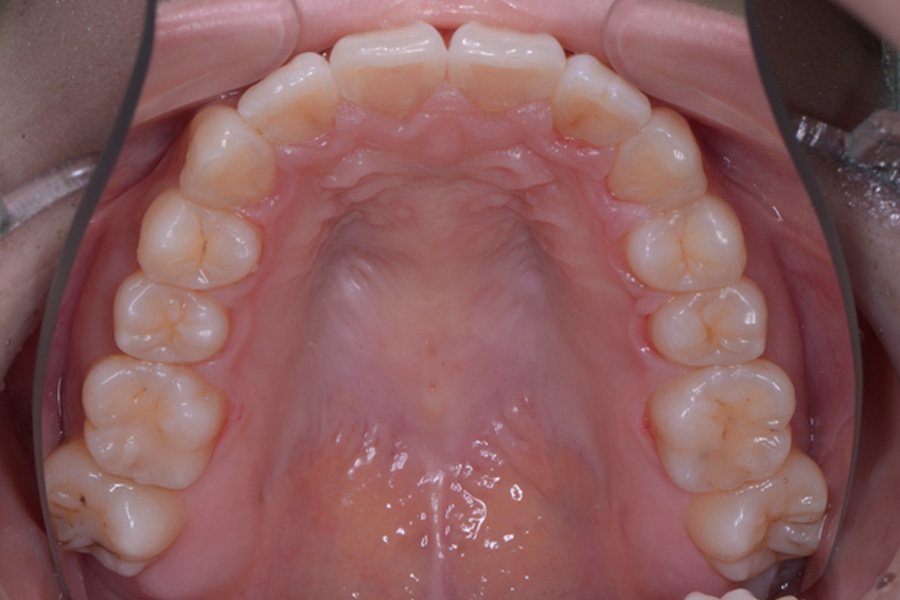

【20代女性】

飛び出ている2本の歯を引っ込めて

下の捻じれている歯を並べたい

治療前

主訴 飛び出ている2本の歯を引っ込めて下の捻じれている歯を並べたい

治療内容 ハーフリンガル矯正(上顎裏側・下顎表側矯正)